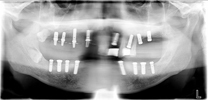

レントゲン写真

治療前 レントゲン写真

治療後 レントゲン写真